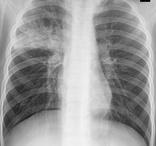

小兒支氣管肺炎

支氣管肺炎是小兒的一種主要常見病,尤多見于嬰幼兒,也是嬰兒時期主要死亡原因。支氣管肺炎又稱小葉肺炎,肺炎多發生于冬春寒冷季節及氣候驟變時,但夏季并不例外,甚至有些華南地區反而在夏天發病較多。支氣管肺炎由細菌或病毒引起。